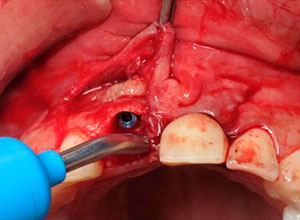

Sindesmotomía del tejido

Extracción, limpieza y curetaje del alveolo

Material osteogénico en masa

Sutura y reconstrucción del tejido blando papilar